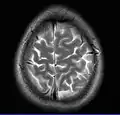

This axial T2-weighted (CSF white) MR scan shows a normal brain at the level of the lateral ventricles.

• T2-weighted (T2W) images: CSF is light, but fat (and thus white matter) is darker than with T1. T2-weighted images are useful for visualizing pathology.[26]